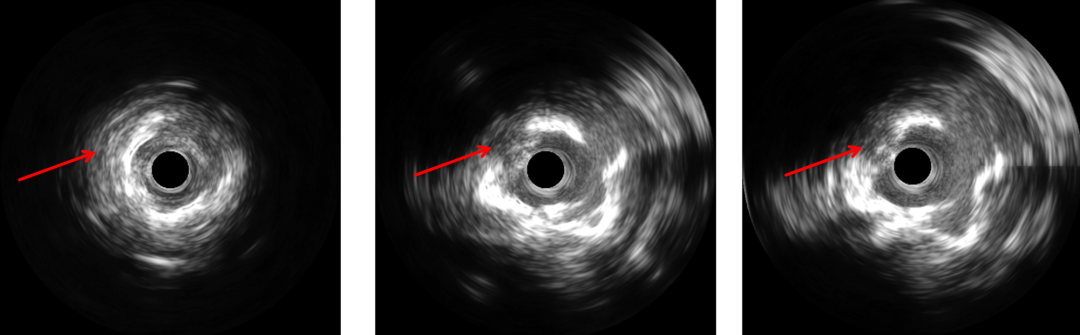

PCI过程-IVUS

IVUS可见钙化变薄、环形钙化断裂